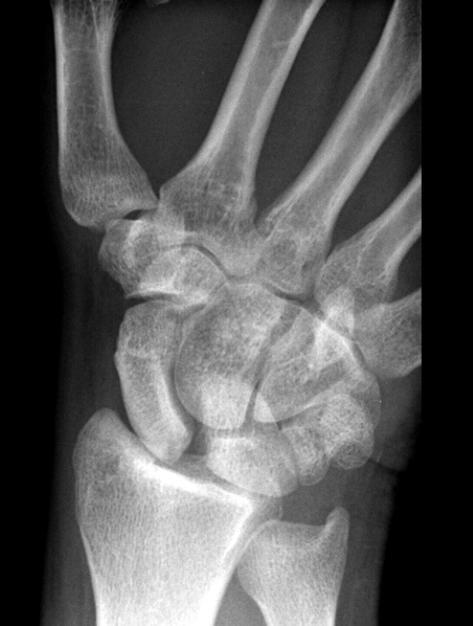

Welche Pathologie erkennen Sie auf folgendem Röntgenbild? Welche Bänder sind bei eben diese Pathologie gerissen?